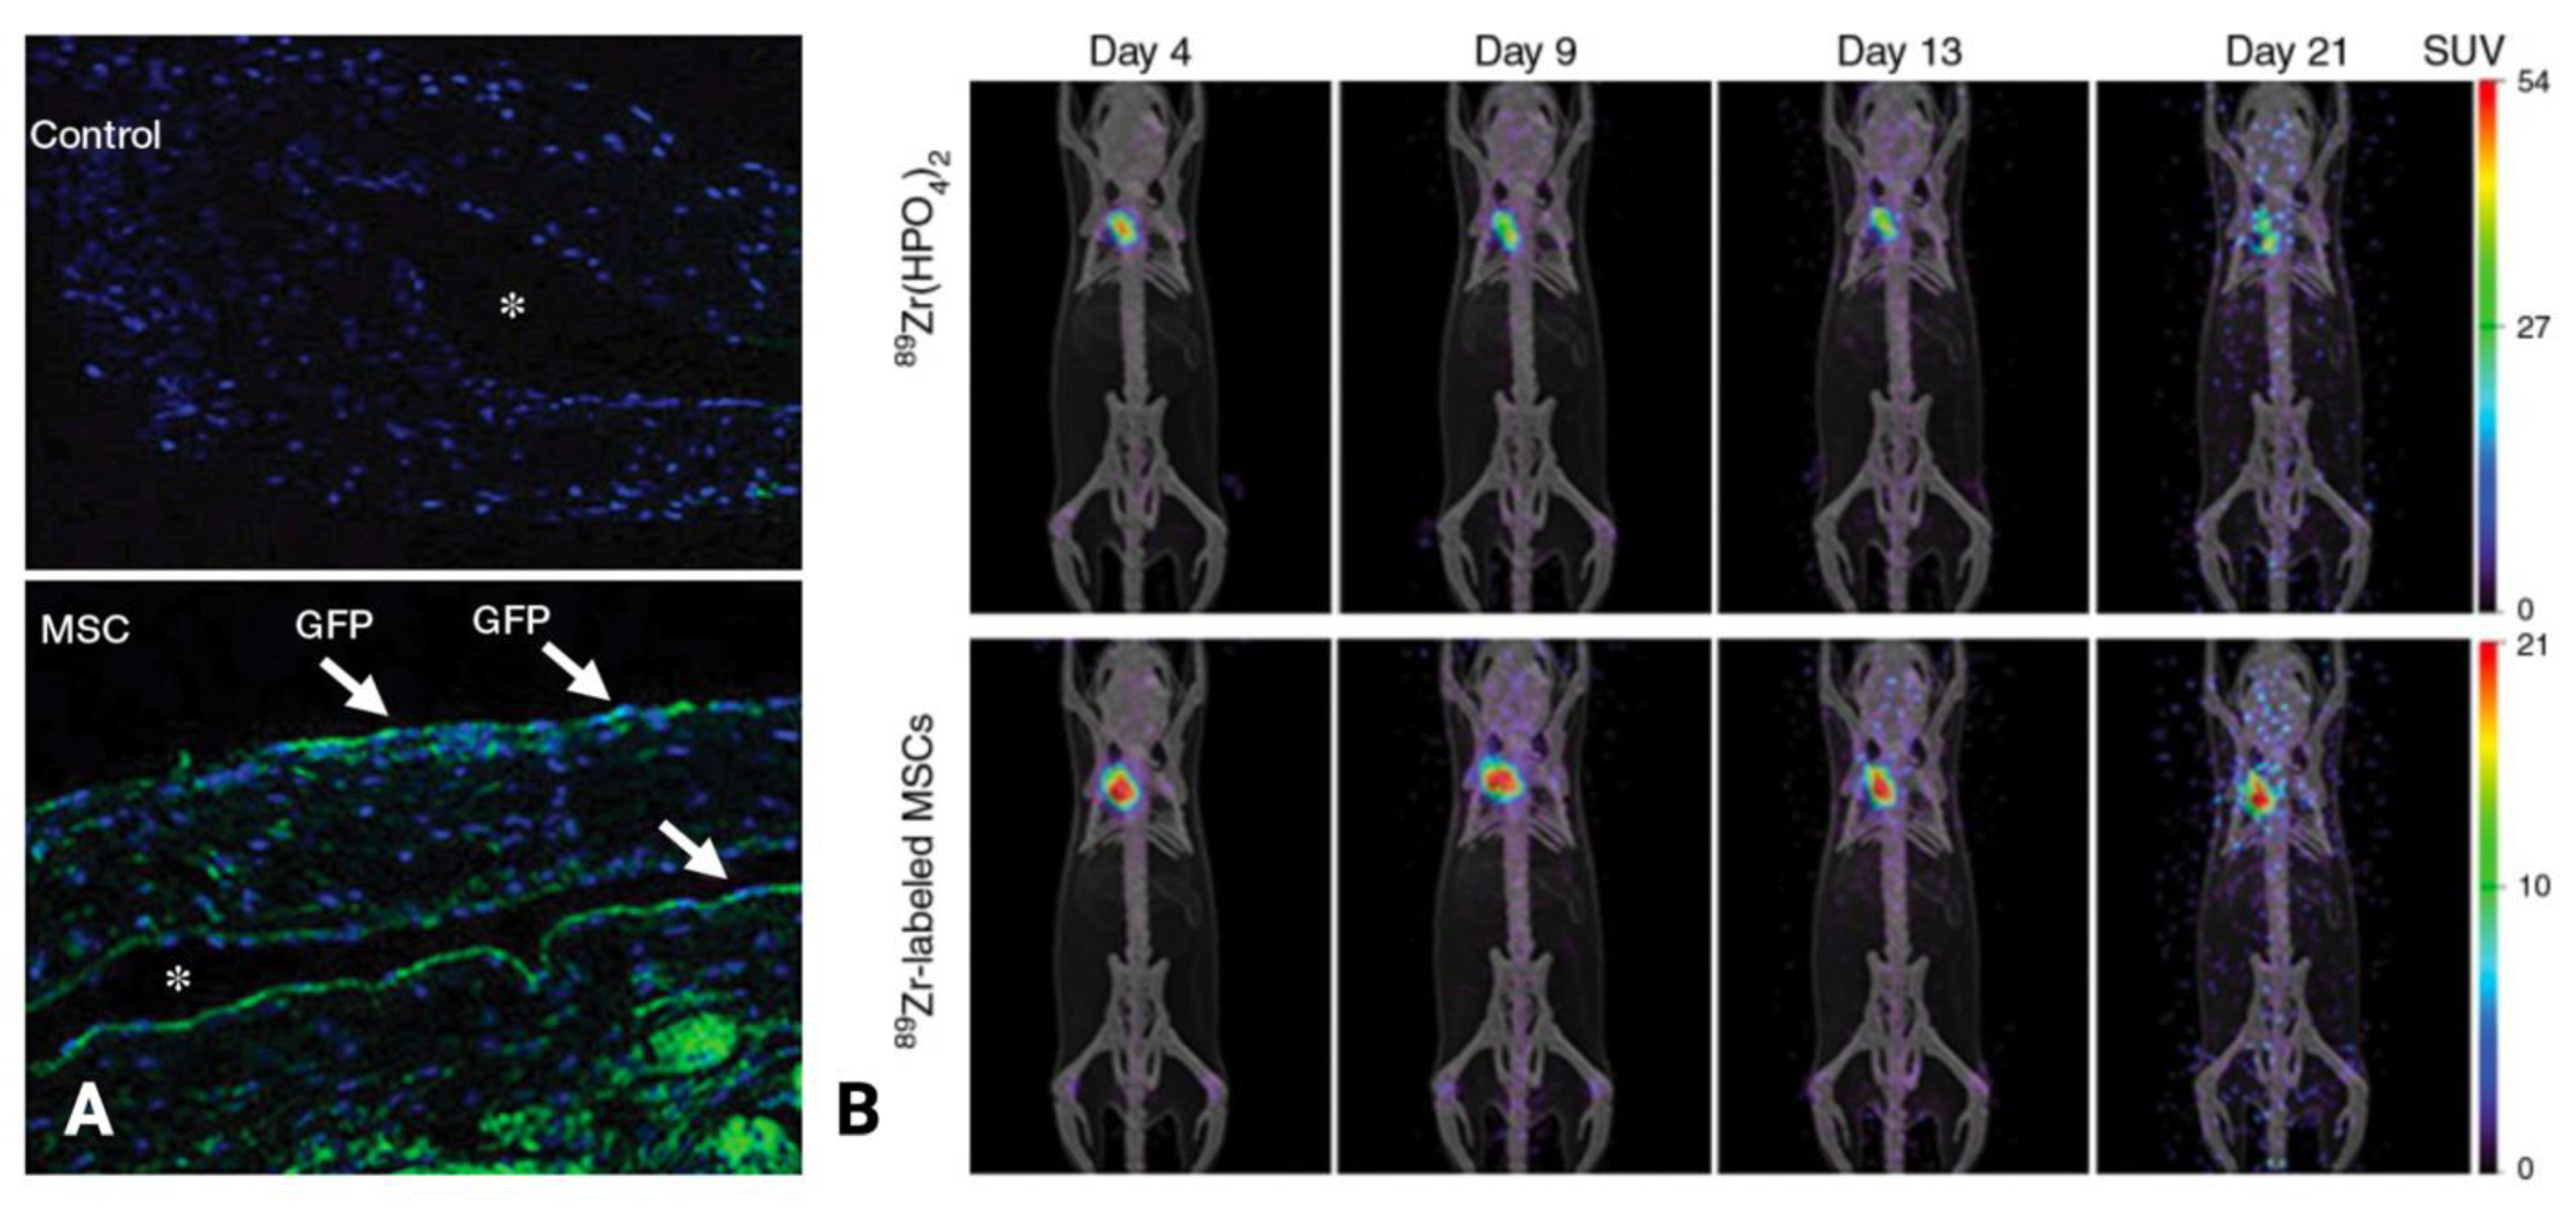

- Yang, B.; Brahmbhatt, A.; Torres, E.N.; Thielen, B.; McCall, D.L.; Engel, S.; Bansal, A.; Pandey, M.K.; Dietz, A.B.; Leof, E.B.; et al. Tracking and Therapeutic Value of Human Adipose Tissue–Derived Mesenchymal Stem Cell Transplantation in Reducing Venous Neointimal Hyperplasia Associated with Arteriovenous Fistula. Radiology 2015, 279, 513–522. [Google Scholar] [CrossRef]

| Mesenchymal stem cell | Preclinical (Murine) | Direct injection into the adventitia significantly reduced the expression of MCP-1 and HIF-1α, increased the mean luminal area, and reduced the mean neointimal area and neointimal cell density | Yang et al. (2015) [61] | |